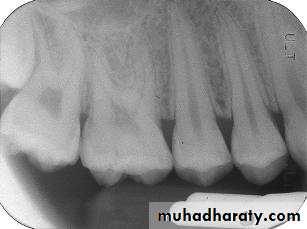

• Indications:• Interproximal caries.

• Over-hang filling.

• Level of crestal bone between the teeth.

• Interproximal calculus.

• The film is placed in the mouth parallel to the crown of both upper & lower teeth.

• The film stabilized when the patient bites on the bite-wing tab or bite-wing film holder.

• The central ray of the x-ray beam is directed through the contacts of the teeth, using a +10 degree vertical angulation.

+10o vertical angulation is used to compensate for the slight bend of the upper portion of the film and the tilt of the maxillary teeth.

Premolar bitewing. A, Film placement. B, Resultant radiograph.

AB